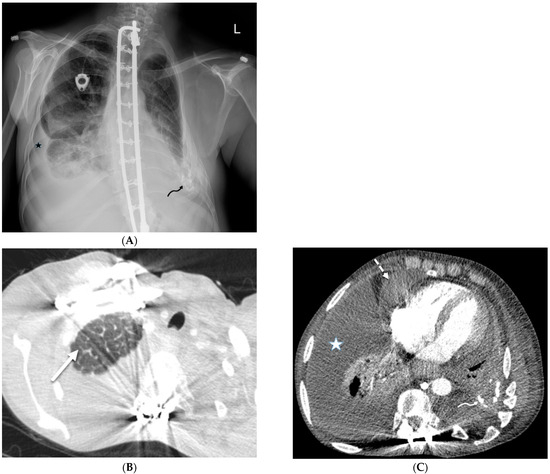

5.4. Leukemia

- Shroff, G.S.; Truong, M.T.; Carter, B.W.; Benveniste, M.F.; Kanagal-Shamanna, R.; Rauch, G.; Viswanathan, C.; Boddu, P.C.; Daver, N.; Wu, C.C. Leukemic Involvement in the Thorax. Radiographics 2019, 39, 44–61. [Google Scholar] [CrossRef]

| Lymphoma | nodular | ++ | +/− | + | +/− | − | ++ | − | − | + |